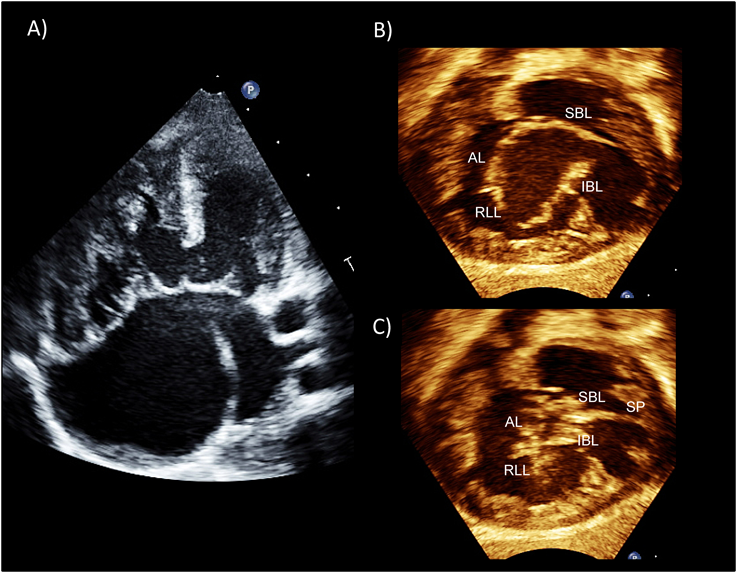

Pediatric Cardiology and Cardiac Surgery 33(2): 140-156 (2017)

Fig. 9 Normal tricuspid valve

(A) Normal tricuspid valve of a neonate. (B) Three-dimensional echocardiography of the normal tricuspid valve (atrial view). AL: anterior leaflet; APM: anterior papillary muscle; AS-com: antero-superior commissure; AP-com: antero-posterior commissure; MPM: medial papillary muscle; PAV: pulmonary valve; PL: posterior leaflet; PPM: posterior papillary muscle; PS-com: postero-septal commissure; SL: septa leaflet.

Fig. 9に新生児の正常三尖弁と経食道3次元エコーでの正常三尖弁を示す.三尖弁は文字通り3弁構造をとるのが通常であるが,正常においても個体間での差異が僧帽弁と比較して大きく,2弁形態や4弁形態をとることもある.三尖弁前尖(anterior leaflet/superior leaflet)は3弁のなかで最も弁葉面積が大きく,前上方に位置し,右室流出路の入り口への暖簾のように存在する.三尖弁中隔尖(septal leaflet/medial leaflet)は前尖に次いで大きい弁葉面積を持つ.中隔尖の腱索は心室中隔から直接起始することから,心室中隔に張り付いた状態で存在し可動性に乏しい.正常の僧帽弁では腱索が心室中隔に挿入することはないことから,中隔尖のこの特異的な形態が三尖弁を特徴づけるものであり,僧帽弁との解剖学的な鑑別点となる.後尖(posterior leaflet/inferior leaflet)は最も弁葉面積が小さく,下壁側に位置する.三尖弁の弁輪には明確な線維性の索状構造が存在しないことが多く,弁の線維性組織はそのまま心内膜下の線維性組織に連続する.特に中隔尖の前方は弁のヒンジ部が房室接合部の高さから心尖方向に偏位したうえで膜様部中隔にそのまま連続することから,弁輪に相当する組織が存在しない.前尖と中隔尖の交連(antero–septal commissure: AS-com)は膜様部中隔の最も頭側に位置し,この交連を支える腱索は通常medial papillary muscle complex(Lancisi’s muscle)(MPM)から起始する.MPMは通常trabecula septomarginalis(TSM)の前腕と後腕の分岐部に位置するが,乳頭筋が複数のこともあれば,乳頭筋構造が全く存在せず,腱索がTSMもしくは室上稜から直接起始する場合もある.前尖と後尖の交連(antero–posterior commissure: AP-com)は右室の鋭縁部に位置し,この交連下に前乳頭筋(anterior papillary muscle: APM)が存在する.この乳頭筋は右室内で最大の乳頭筋であり,基部に調節帯(moderator band)を持つ.後尖と中隔尖の交連(postero–septal commissure: PS-com)は右室下壁と中隔の移行部に存在し,その下部に後乳頭筋(posterior papillary muscle: PPM)が存在する.この乳頭筋は下壁中隔側に存在し,小さい乳頭筋であることが多いがサイズは個体差が大きい16)